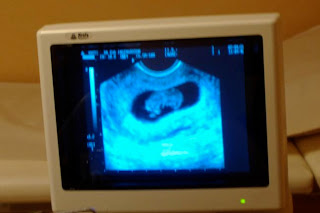

I vecka 9 gjorde vi ett VUL, jag var nära att kräkas så nervös som jag var.

När jag så såg den 2,9 cm lilla räkan röra sig därinne i min mage blev jag förälskad.....

Tänk att det bodde ett litet barn i mig. Tänk att vi skulle bli föräldrar. Så häftigt!